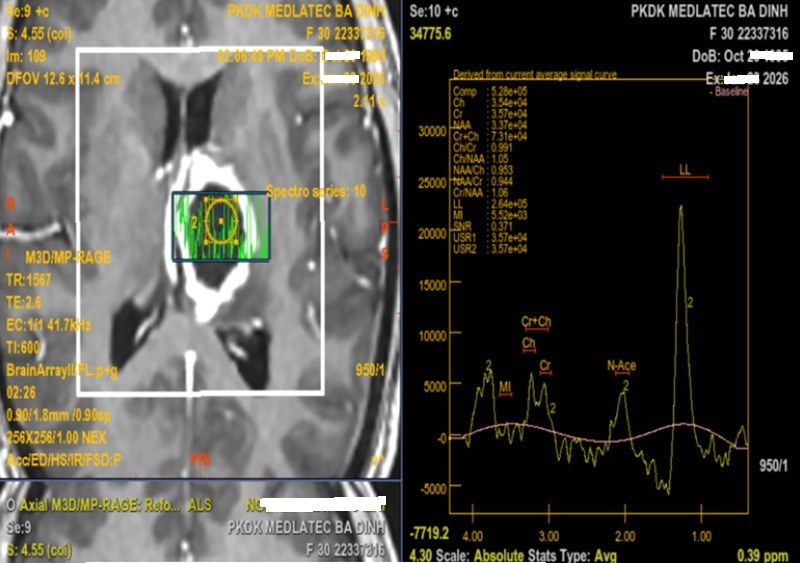

Chụp cộng hưởng từ (MRI) sọ não, bác sĩ phát hiện tổn thương khu trú tại vùng đồi thị – vành tia bên trái. Tổn thương dạng dịch, kích thước khoảng 26x37x25 mm, ranh giới rõ, bờ không đều, phần trung tâm hạn chế khuếch tán, sau tiêm ngấm thuốc viền, vùng xung quanh xuất hiện phù não, gây hiệu ứng khối làm đẩy lệch đường giữa sang phải khoảng 5mm. Chụp cộng hưởng từ phổ cho thấy, giảm Choline và NAA, tăng Lipid và Lactate.

Kết quả chụp cộng hưởng từ phổ của bệnh nhân

Bên cạnh đó, cộng hưởng từ phổ (MRS) cung cấp thêm thông tin về thành phần chất chuyển hóa trong tổn thương. Với áp xe não, MRS ghi nhận tăng các đỉnh Lactate và Lipids – sản phẩm của quá trình chuyển hóa yếm khí và hoại tử mô, đồng thời giảm các chất chuyển hóa đặc trưng của mô não như NAA, Choline và Creatine.